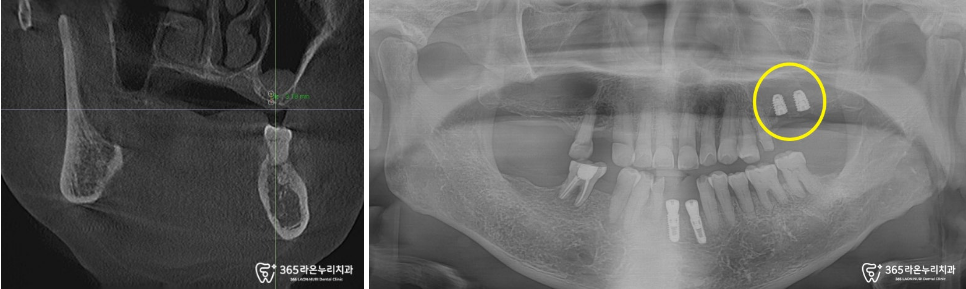

치료 전, CT로 남아 있는 뼈의

상태 확인도 잊지 않았습니다.

왼쪽 위턱의 뼈 양을 확인하고,

상악동 거상술로 임플란트 픽스처가

들어갈 공간 확보 및 뼈이식 과정을 함께

진행해드렸습니다!

임플란트 픽스처가 계획된

자리에 안정적으로 심어진 모습이

관찰되고 있습니다.